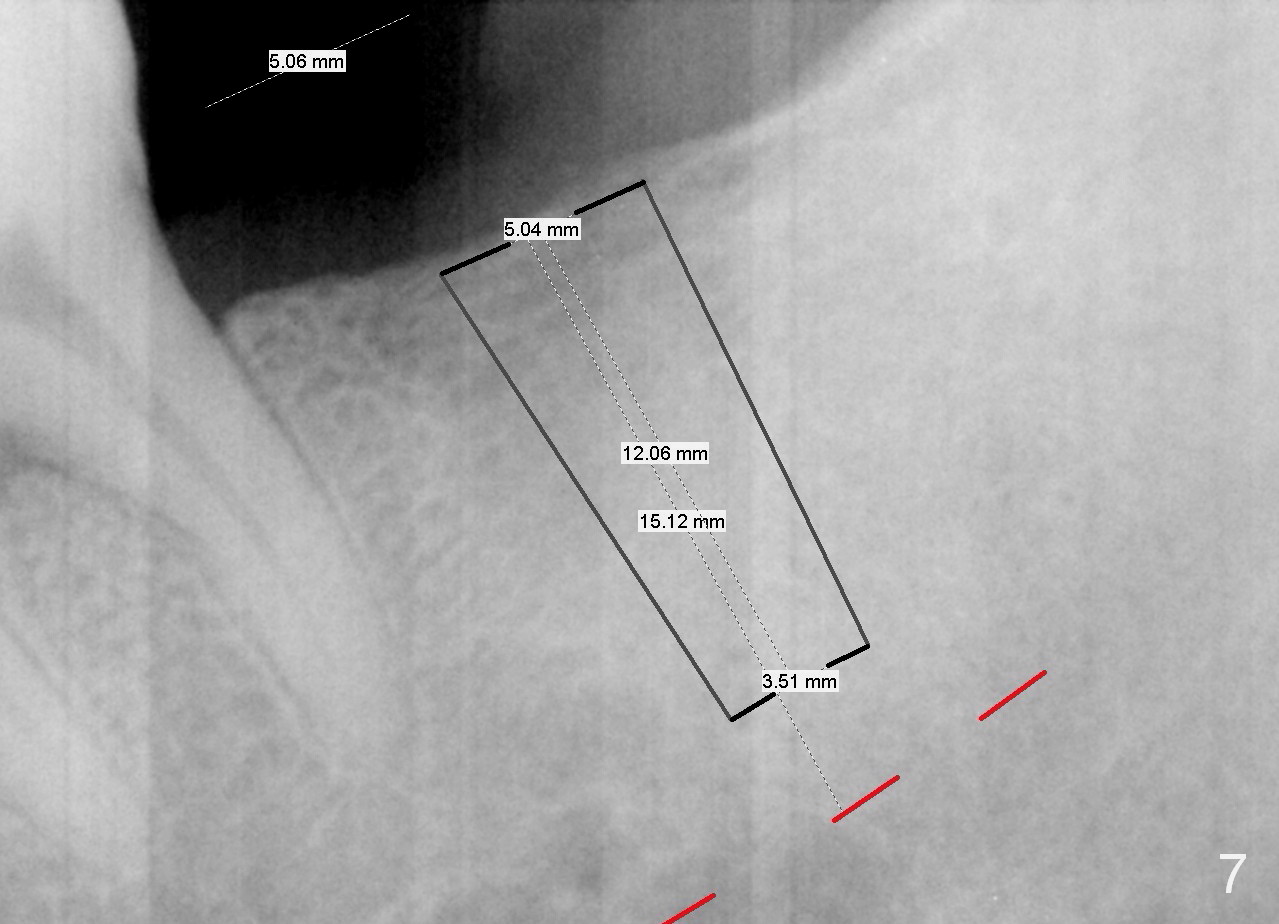

A 51-year-old man has lost #18 for more than 10 years (Fig.1,6). There appears to be sufficient bone height for implant (15 mm (Fig.7 (red dashed line: the superior border of the Inferior Alveolar Canal))). Prepare 4 mm implant spacer and SM starter drill and 2 mm pilot drill at 12 mm. Take PA. Palpation reveals that the edentulous ridge is wide. Place an implant in the middle of the ridge (buccolingually).